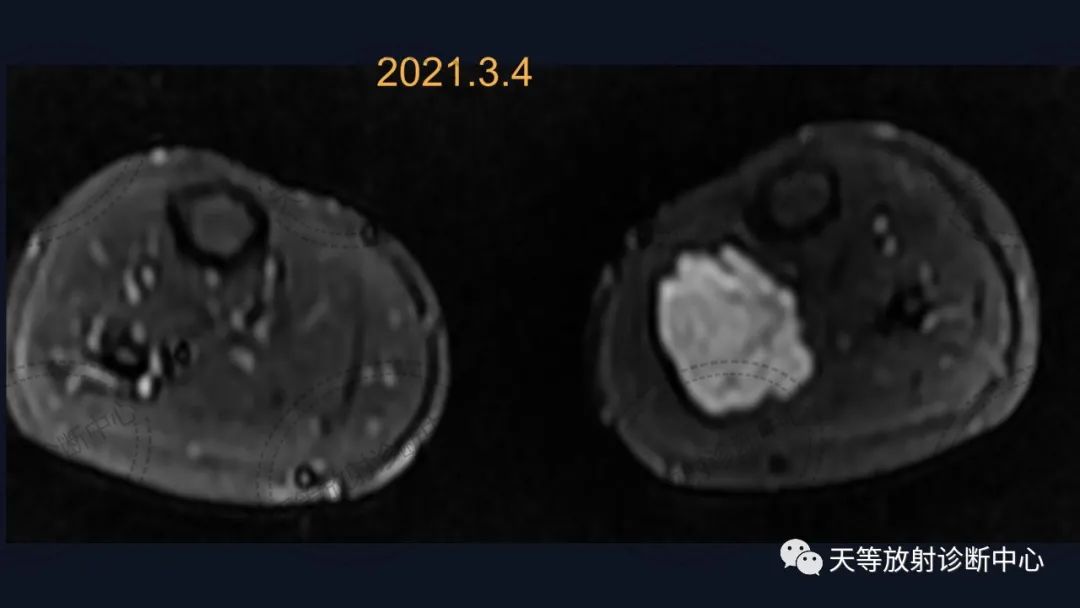

病例,儿童男性

前后两次对比观察,病灶略有增大。

组织学上主要表现为血管管道数目的增加及纤维结缔组织、平滑肌、炎性细胞和毛细血管、淋巴管等不同程度的浸润。MRI观察病灶内纤维结缔组织呈分隔状及线状低信号影,含血管成分可表现血管流空信号影。病灶内出血表现信号混杂等。